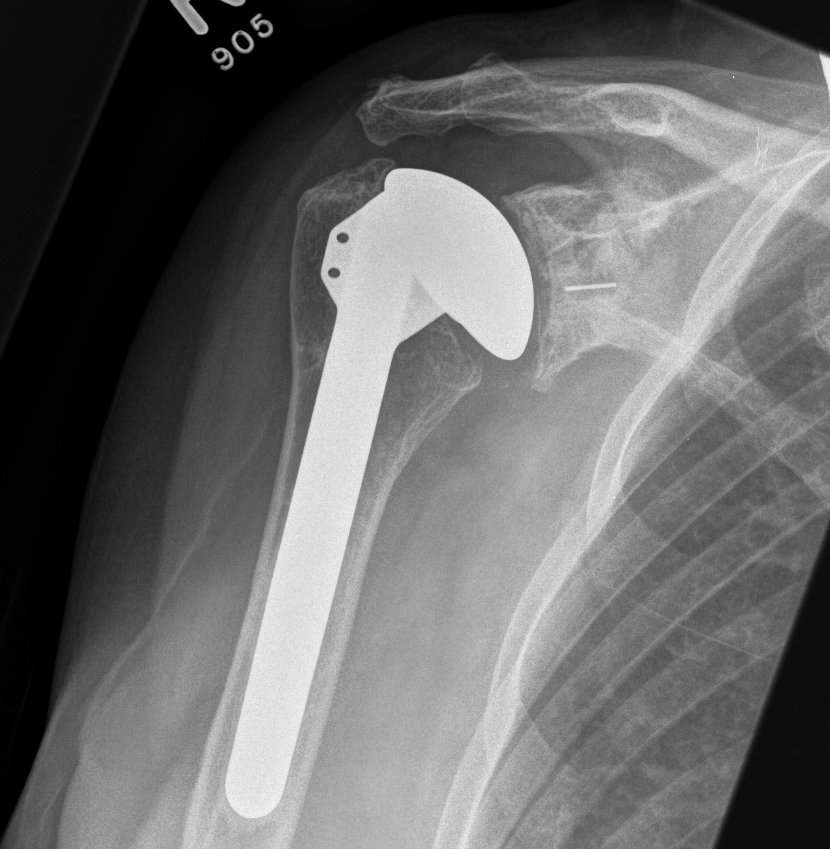

Anatomical Total Shoulder Design

Stem

Stemmed versus short stems versus stemless

Australian Joint Registry 2024

- 12,000 aTSA for OA

- 10 year revision rate stemmed 13%

- 10 year revision rate stemless 14%

Fixation

Glenoid design

Cemented all poly versus uncemented metal back glenoid

Significantly higher revision rate will metal verus poly glenoids

- Australian Joint Registry

- 11,000 aTSA at 5 years follow up

- revision rate cemented glenoid 3.7%

- revision rate uncemented 17.9%